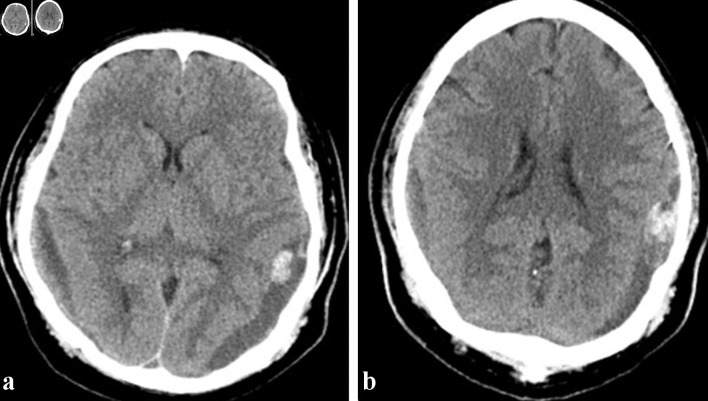

Intracerebral hemorrhage is a potentially fatal complication in patients with acute leukemia and contributing factors include thrombocytopenia and coagulopathy. Patients with acute leukemia may develop subdural hematoma (SDH) spontaneously or secondary to trauma. In patients with acute leukemia and SDH, the surgical evacuation of the hematoma causes significant morbidity and mortality. New approaches and strategies to reduce the need for surgical evacuation are needed to improve outcomes in patients with acute leukemia and intracerebral hemorrhage. We report two cases of acute SDH in patients with acute leukemia successfully treated with middle meningeal artery embolization, a minimally invasive interventional radiology technique, obviating the need for a surgical intervention. The first patient with acute promyelocytic leukemia (APL) presented with coagulopathy and developed an acute SDH after a fall. The second patient with acute myeloid leukemia presented with gum bleeding and also sustained an acute SDH after a fall. Both patients underwent middle meningeal artery embolization for treating their SDHs while actively receiving induction chemotherapy for acute leukemia. Both patients had resolution of their acute SDH and are in remission from their acute leukemia. Middle meningeal artery embolization is a very effective, and within the context of this setting, a novel, minimally invasive technique for management of SDH in acute leukemia patients, which can prevent the need for surgical interventions with its associated comorbidities and high risk of fatal outcomes in patients with acute leukemia and acute SDH.

Abstract Image